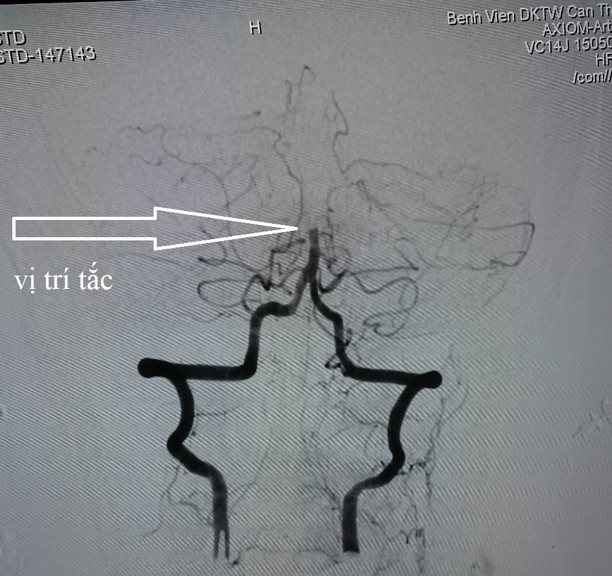

Hình ảnh đột quỵ do tắc động mạch thân nền